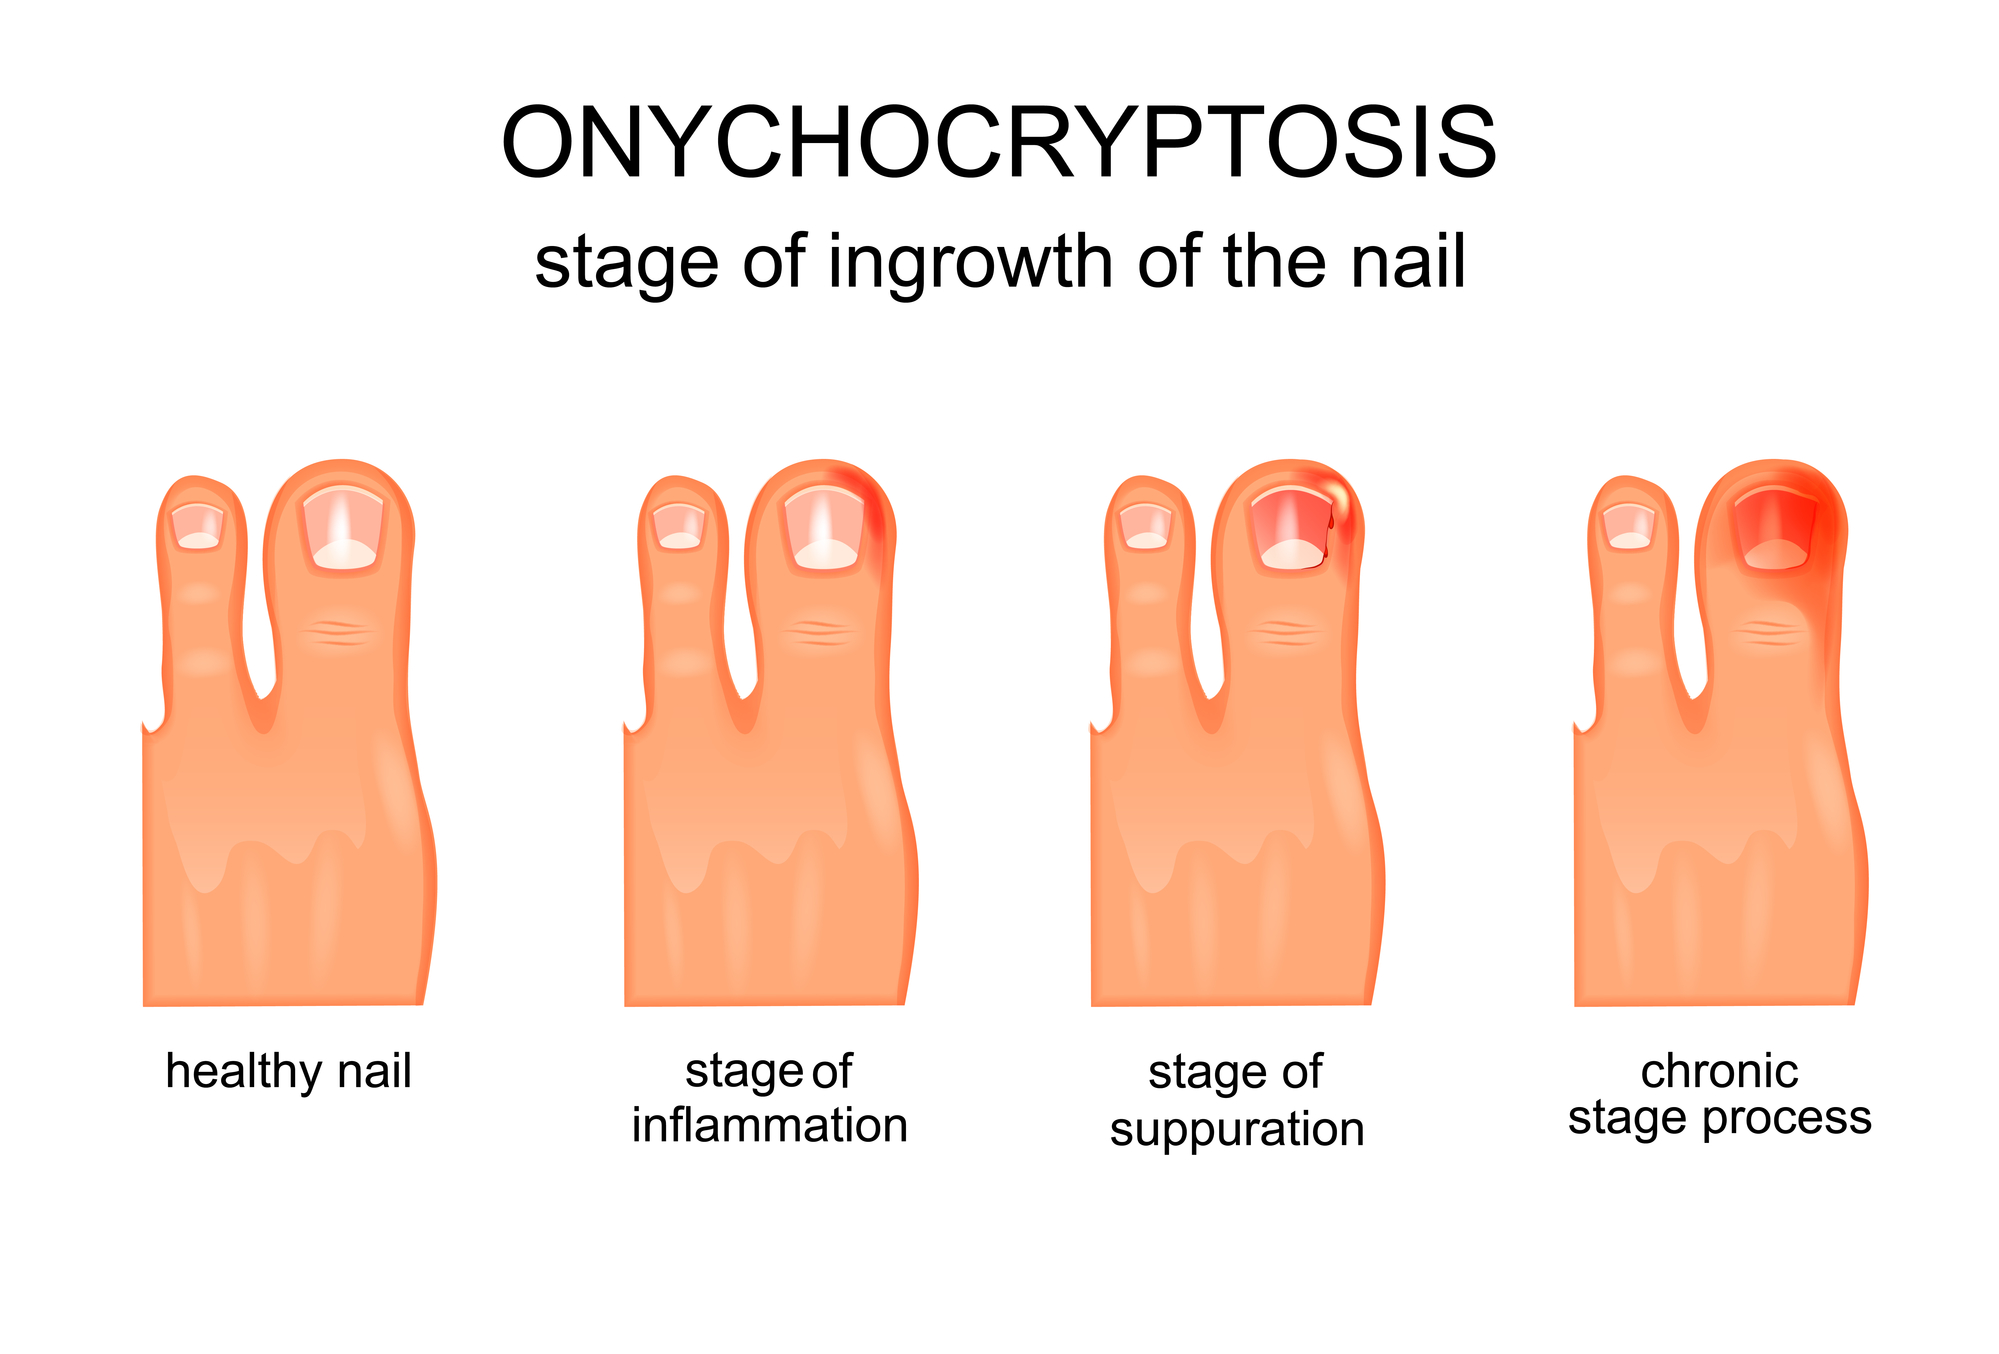

Ingrown Toenail

Details Of The Ingrown Nail Diagnosis Download Scientific Diagram